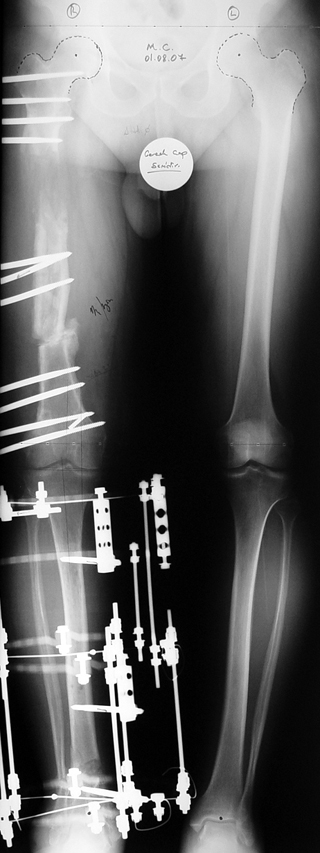

Case 2